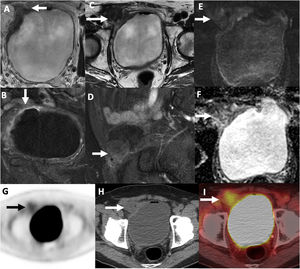

(A–F) Contrast-enhanced MRI of the bladder after transurethral resection (TURB). (A) Axial T2-weighted, (B) axial T1-FS contrast enhanced, (C) axial T2-weighted, (D) sagittal T1-FS without contrast, (E) DWI, b value: 1000, (F) ADC map. No residual bladder malignancy (short arrows) was identified on T2-weighted (A) or contrast-enhanced (B) sequences. The right inguinal hernia mesh-plug initially delineated on CT (arrows on C–F) was an irregular solid lesion hypointense on T2-weighted images (C), without contrast-enhancement (D) or restricted diffusion (E: B1000, F: ADC map), representing granulation tissue from the prior hernia repair. G–I: 18FDG PET/CT after TURB. (A) PET, (B) PET/CT fused, (C) CT. The right inguinal hernia plug (arrows) had low-level tracer uptake (SUV: 2.6g/ml) on PET (G) and fused PET/CT (I) and was isodense to muscle on non-contrast CT (H), supporting the diagnosis of granulation tissue.

In the patient presented, there is an anterior-superior bladder wall tumor and a mass-like lesion due to granulation tissue in the inguinal ring. The review of the patient's history, visualization of the overlying postsurgical changes at the inguinal ring, along with the delineation of the features described on CT, MRI, and PET/CT, led to the appropriate diagnosis and aided in the clinical management.